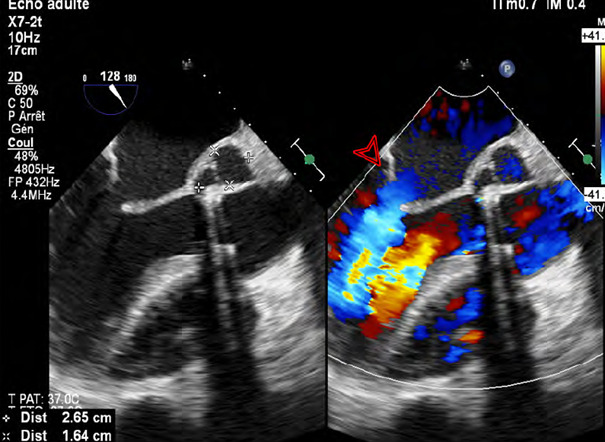

Observation: This clinical case concerns a 59-year-old man with a mechanical aortic prosthesis who presented with heart failure with prosthetic disconnection, aortic annulus abscess, and negative blood cultures. The diagnosis was confirmed by serologic testing and culture of the surgical specimen, which revealed infection with B. melitensis associated with consumption of unpasteurized raw milk. Treatment required surgery to replace the prosthesis and drain the abscess, and prolonged antibiotic therapy with doxycycline, cotrimoxazole, and rifampicin. Despite postoperative complications, hemodynamic and infectious outcomes were favorable.

Conclusion: This case highlights the importance of a multidisciplinary approach, including targeted serologic testing and cardiac imaging, for early diagnosis. It also emphasizes the need for surgical management combined with appropriate antibiotic therapy to improve the prognosis of patients with BE.